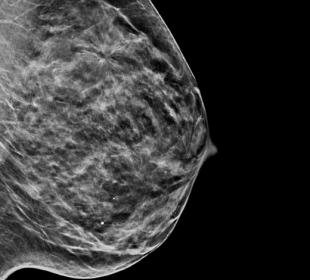

Breast Health

Hologic is transforming breast care. We apply cutting-edge science to accelerate discovery, improve efficiency and continually sharpen precision.

Breast Health Continuum of Care

Time is precious when it comes to effective detection, diagnosis and treatment of breast cancer. We strive to save you time at every step along the Continuum of Care.